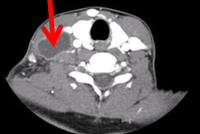

TC donde se observa un ganglio linfático cervical necrótico

De la colección de Dr David J. Horne y Dr Masahiro Narita; usado con permiso